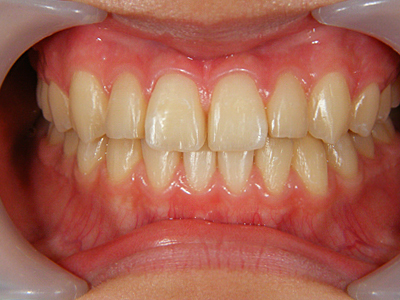

11. 術後正面

矯正装置による動的移動を終え、ブラケットを除去して歯冠研磨した後の正面写真です。ブラケット装着期間は約2ヶ月強。その間は毎週来てもらいました。もちろん早ければ良いというわけではなく、無理な歯牙移動はさまざまな弊害をもたらします。後は可徹式の保定装置を作製します。